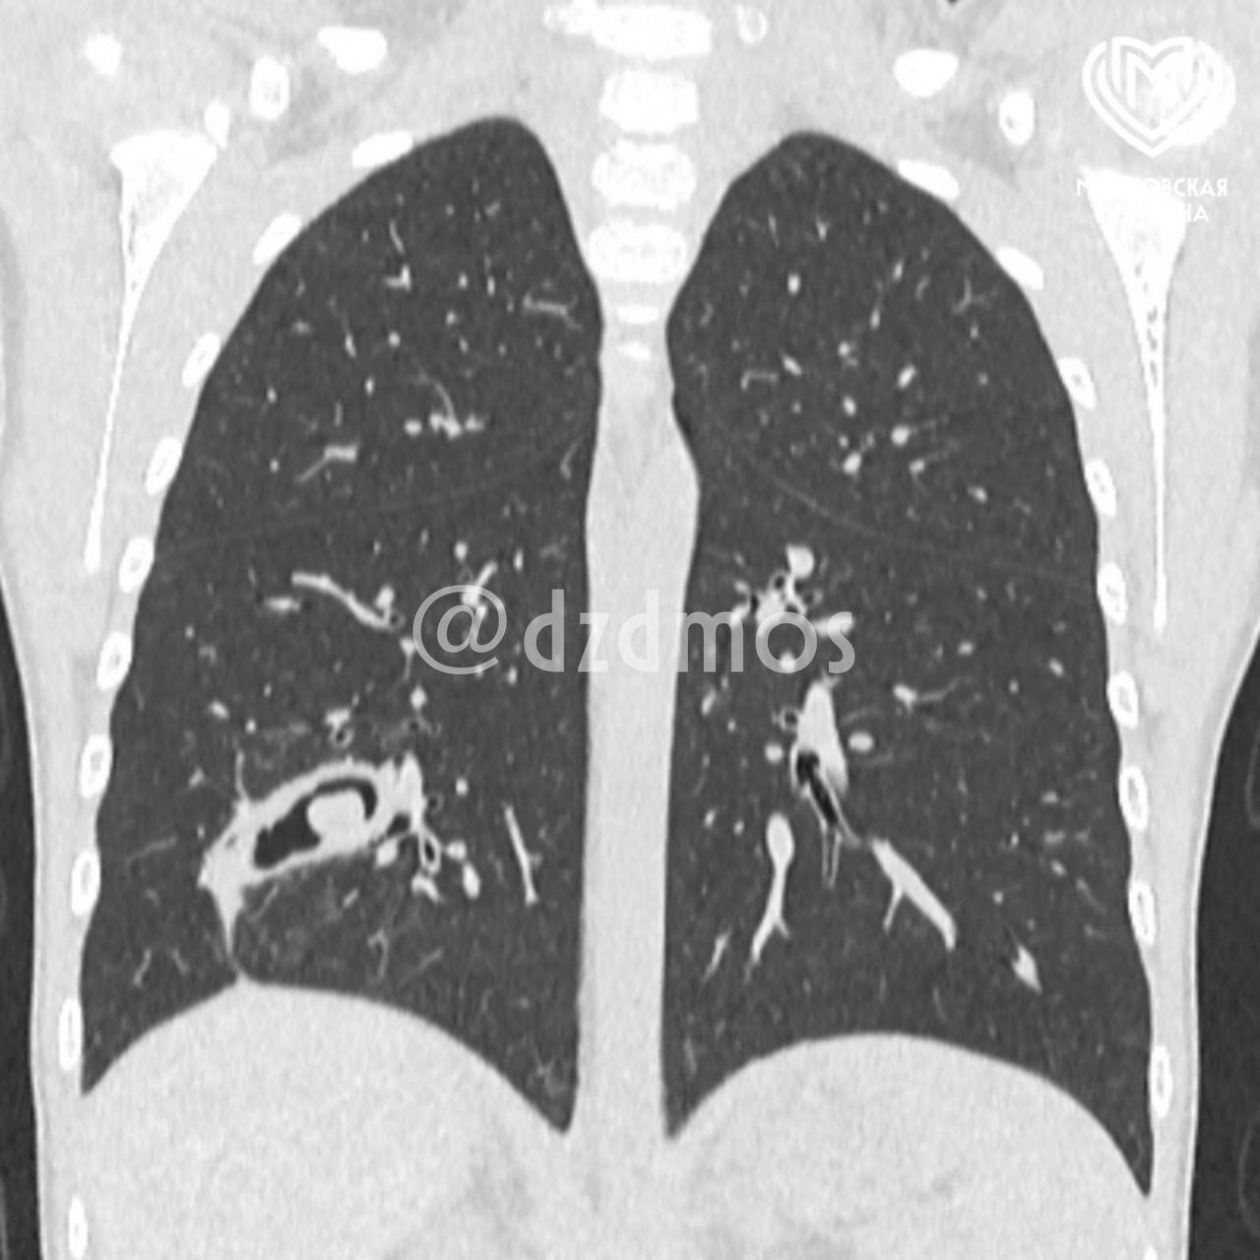

Снимок легкий юной пациентки. Фото: Telegram-канал "Московская медицина"

Детский хирург, заместитель главного врача по хирургической помощи Дмитрий Еремин рассказал, что обследование и КТ показали серьезные изменения в бронхах. По его словам, часть скорлупы впаялась в третий субсегмент правого легкого, из-за чего у девочки образовался бронхоэктаз — участок, в котором бронхи перестали нормально функционировать из-за скопления гноя.